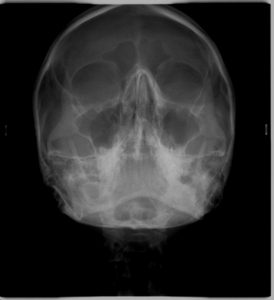

4. ΑΚΤΙΝΟΓΡΑΦΙΑ ΙΓΜΟΡΕΙΩΝ WATERS

Πρόκειται για κατά μέτωπο ακτινογραφία του κρανίου, η οποία λαμβάνεται με την κεφαλή του εξεταζομένου να βρίσκεται σε κλίση 45 μοιρών προς τα άνω.

Είναι χρήσιμη για τη μελέτη κυρίως των ιγμορείων άντρων και των μετωπιαίων κόλπων.